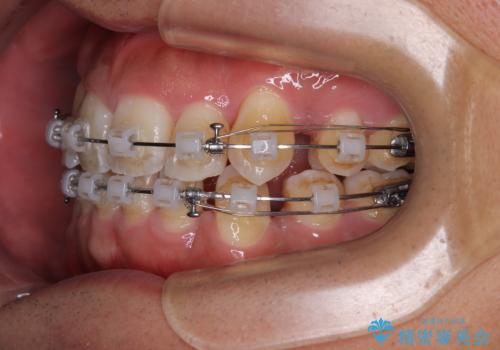

矯正装置は、審美性と費用面のバランスを考慮して、プラスチックブラケットとメタルワイヤーを使用しました。

透明感のあるブラケットを用いたため、従来の金属装置よりも目立ちにくく、日常生活での見た目の不安も軽減できます。